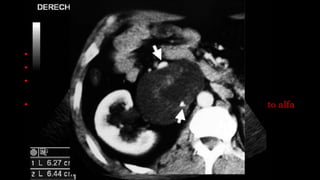

TU. PRODUCTOR DE CATECOLAMINAS •Feocromocitomas y paragangliomas. • Producen HTA de difícil tratamiento. • Los medio de contraste producen exacerbación de los síntomas. • Una semana antes del estudio comenzar con tratamiento alfa o beta bloqueante.